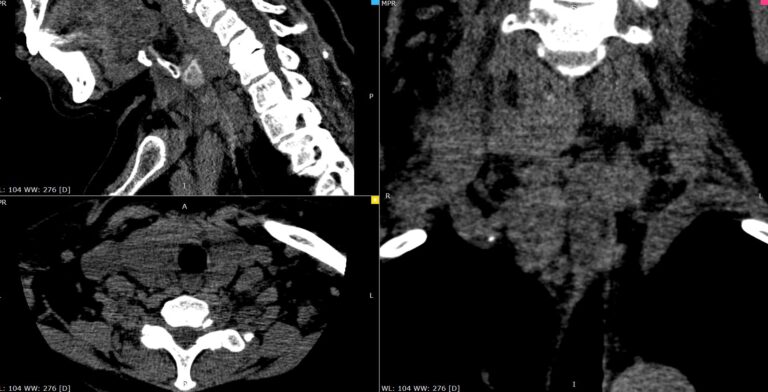

Мультиспиральная компьютерная томография позволяет точно определить размеры и расположение паращитовидных желез, в том числе при атипичном их расположении (загрудинно, в средостении), выявить опухолевые образования, оценить их структуру, степень кровоснабжения, взаимодействие с окружающими тканями.

В клинике «Доступная медицина» данное исследование выполняется по трем различным протоколам (в нативную, раннюю артериальную и позднюю венозную фазы сканирования). Это соответствует современным мировым стандартам, применяемым для наиболее точного определения характера выявленных образований, в частности, позволяет отличить злокачественные опухоли от доброкачественных.

Обследование проводится на мультиспиральном 128-срезовом томографе экспертного класса TOSHIBA AQUILION CXL. Аппарат выполняет послойное сканирование исследуемой области с толщиной среза от 0,5 мм. Увеличенное количество детекторов позволяет максимально сократить время исследования при минимальной лучевой нагрузке на пациента. При этом сканер дает детальную информацию о зоне исследования, а современные компьютерные программы преобразуют полученные данные в 3D-изображения высокого качества.

При отсутствии патологических изменений паращитовидные железы могут быть практически не видны, поэтому для их визуализации обязательно применяется контрастное усиление. Для этого пациенту внутривенно вводится йодсодержащий контрастный препарат. Контрастное вещество быстро распространяется по кровеносной системе и накапливается в патологических очагах, что хорошо видно на снимках КТ. Таким образом, контрастирование помогает выявлять опухоли на начальной стадии развития, когда лечение наиболее эффективно.